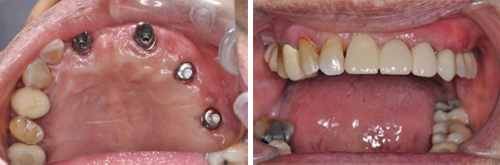

3、即刻修复

根据术前确定的种植方案制备临时修复义齿,手术过程中种植和修复一次完成。

4、最终修复美学效果显著改善

得益于术前的计算机辅助设计,种植修复后的美学效果可以预测,在种植方案规划中综合考虑咀嚼功能和美学功能的协调。